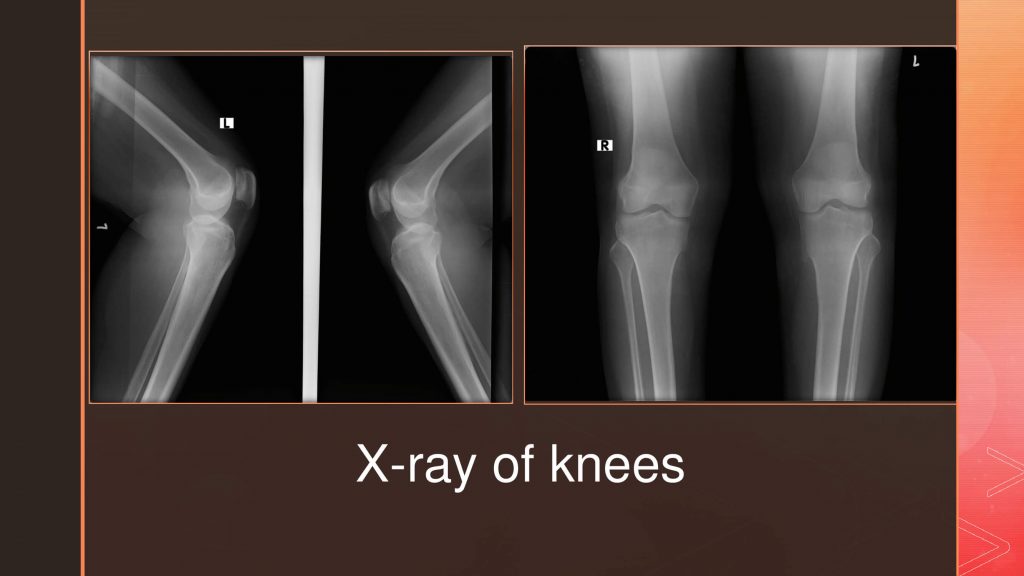

55 years, female presented with back pain of inflammatory nature. She had both knee pain from the age of 40, with episodes of swelling, and inflammatory parameters being significantly elevated. The BMD indicated a significantly low score and no pathological fracture to date, The serum vitamin D levels were also normal. Radiological images of knee joints show normal knee joints, pelvis shows bilateral normal sacroiliac joints.

The present case fulfills the ASAS classification criteria2 (figure 1 & 2) required for axial spondyloarthritis other than age and radiographic features. However, the possibility of spondyloarthropathy is relatively low for these female patients aged above 55 years. Radiographs of the knee and pelvis, and even that of the spine, do not suggest significant degenerative changes. Under the circumstances, one must consider the possibility of Infection including pelvic infection as well the malignancy like Multiple myeloma, as the inflammatory parameters are elevated. Evaluation of electrophoresis suggested an inflammatory pattern. Gynecological evaluation for pelvic infections and malignancy was found to be negative. The patient was HLA B 27 positive and anti-CCP negative.

Spondyloarthropathy, though common in the younger age group, is adequately described in the literature. The clinical spectrum may vary, and age can be up to 70 years.3 The present patient fulfilled the ASAS criteria, in addition to being HLA B 27 positive and having elevated inflammatory parameters whereas the radiographic imaging indicates no damage to the knees and pelvic joints. Axial arthritis with no damage to the sacroiliac joints is considered non-radiographic axial spondyloarthropathy4.